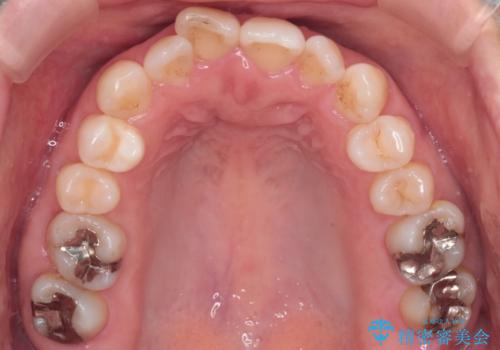

【インビザライン 】前歯のガタガタを治したい

- 前歯のガタガタを主訴に来院されました。

インビザライン で治療しました。途中は使用時間が20時間を切ることもありましたが、それでも頑張って使っていただき1年半で矯正終了することができました。